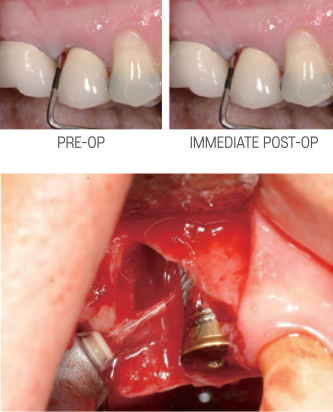

De-Epithelialization and Soft Tissue Management

Gingivectomy, Gum Bleaching, Frenectomy, Crown Lengthening, Fibroma Removal

- Hemostatic effect enables treatment with minimal to no bleeding, often requiring only topical or no anesthesia

- Fast recovery time allows immediate return to normal oral activities

- Allows precise and customized design to match the natural gingival contour

Gum Bleaching

Crown Lengthening – Functional

Contour osseous tissues1 to achieve necessary biologic width

Gingivectomy

No anesthesia necessary in most cases, with highly predictable tissue results